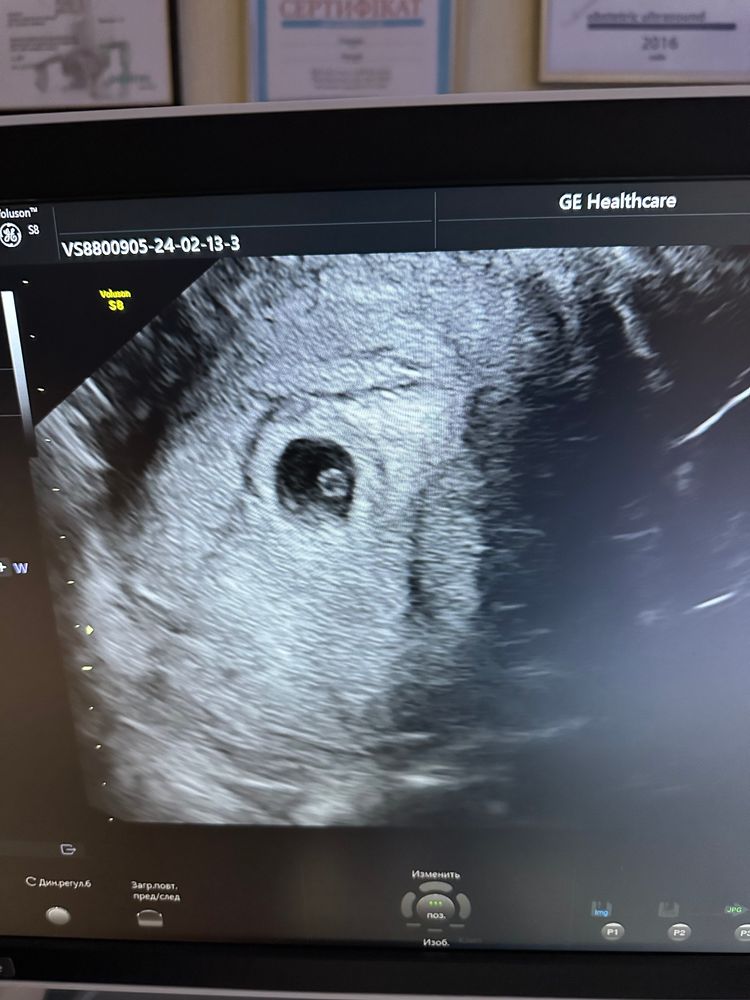

Елена, не подскажите, что это такое на узи? Под ЖМ Изображение Изображение